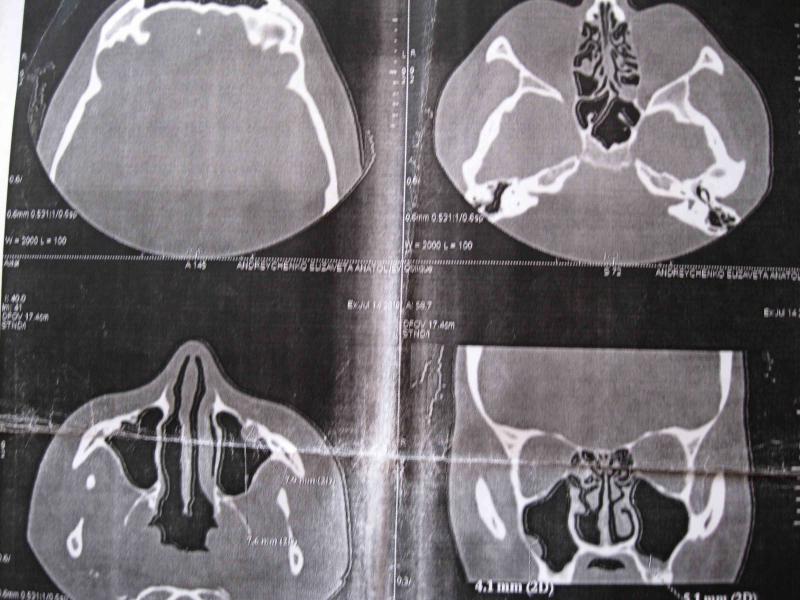

КТ выкладываю. Там разрастание слизистой в решетках и киста в гайморовой пазухе.

Разрастание слизистой в решетках

У Вас типичные симптомы хронического этмоидита в стадии декомпенсации, Вам необходимо пройти обязательный курс антибиотикотерапии. Насчет кист-операция проводится только вне обострений всех заболеваний пазух и только при наличии показаний.